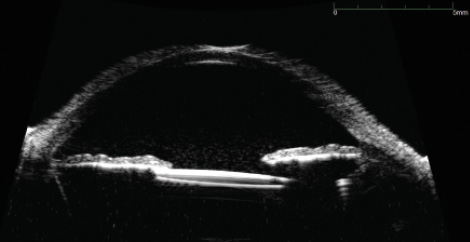

Figure 3. Ultrasound biomicroscopy of the iris-sutured IOL shows significant contact with the iris, causing trauma with pigment dispersion and recurrent hemorrhage.

I diagnosed uveitis-glaucoma-hyphema (UGH) syndrome, likely caused by the iris-sutured IOL’s rubbing on the posterior iris surface (Figures 2 and 3). Another washout was performed as well as an IOL exchange. To move the IOL away from the iris, I replaced the iris-sutured IOL with a sclera-sutured lens. The patient’s UCVA improved to 20/50, but 2 weeks later, the hyphema and vitreous hemorrhage returned. The IOP began to rise into the high 20s despite maximum topical glaucoma medications.